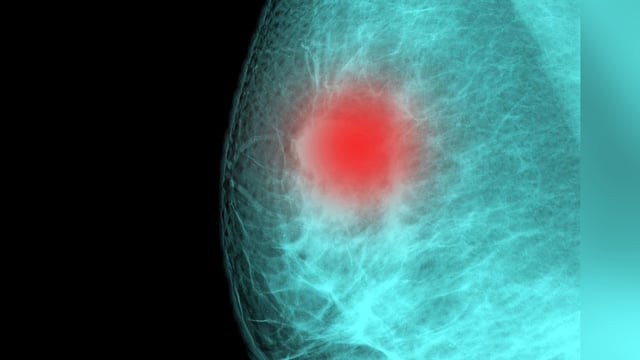

Researchers to Test IL-6 Blockers After Viruses Found to Wake Dormant Breast Cancer Cells

Data from mouse models alongside human registries reveal that IL-6–driven inflammation during flu and COVID-19 infections awakens dormant breast cancer cells in the lungs, spurring planned clinical trials of IL-6 inhibitors.